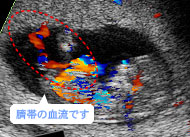

赤と青の帯が血流。母體(tǐ)(胎盤)と胎児は臍帯でつながっているんです。(妊娠12週)

赤と青の帯が血流。母體(tǐ)(胎盤)と胎児は臍帯でつながっているんです。(妊娠12週)